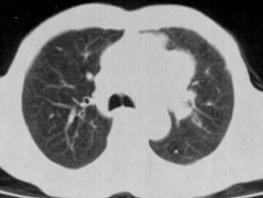

问题 60岁,男,有长期抽烟史,左声带麻痹、声音嘶哑2个月,请结合胸片和CT图.选出最可能的诊断 ( )

选项 A、肺炎 B、肺结节病 C、肺结核 D、尘肺 E、肺癌

答案 E